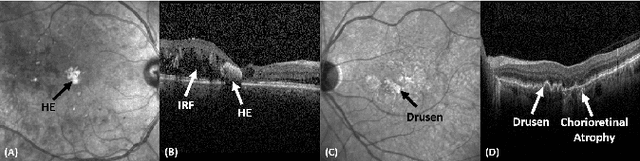

Abstract:Identification of lesions plays a vital role in the accurate classification of retinal diseases and in helping clinicians analyzing the disease severity. In this paper, we present a detailed evaluation of RAGNet, PSPNet, SegNet, UNet, FCN-8 and FCN-32 for the extraction of retinal lesions such as intra-retinal fluid, sub-retinal fluid, hard exudates, drusen, and other chorioretinal anomalies from retinal fundus and OCT scans. We also discuss the transferability of these models for extracting retinal lesions by varying training-testing dataset pairs. A total of 363 fundus and 173,915 OCT scans were considered in this evaluation from seven publicly available datasets from which 297 fundus and 59,593 OCT scans were used for testing purposes. Overall, the best performance is achieved by RAGNet with a mean dice coefficient ($\mathrm{D_C}$) score of 0.822 for extracting retinal lesions. The second-best performance is achieved by PSPNet (mean $\mathrm{D_C}$: 0.785) using ResNet\textsubscript{50} as a backbone. Moreover, the best performance for extracting drusen is achieved by UNet ($\mathrm{D_C}$: 0.864). The source code is available at: http://biomisa.org/index.php/downloads/.